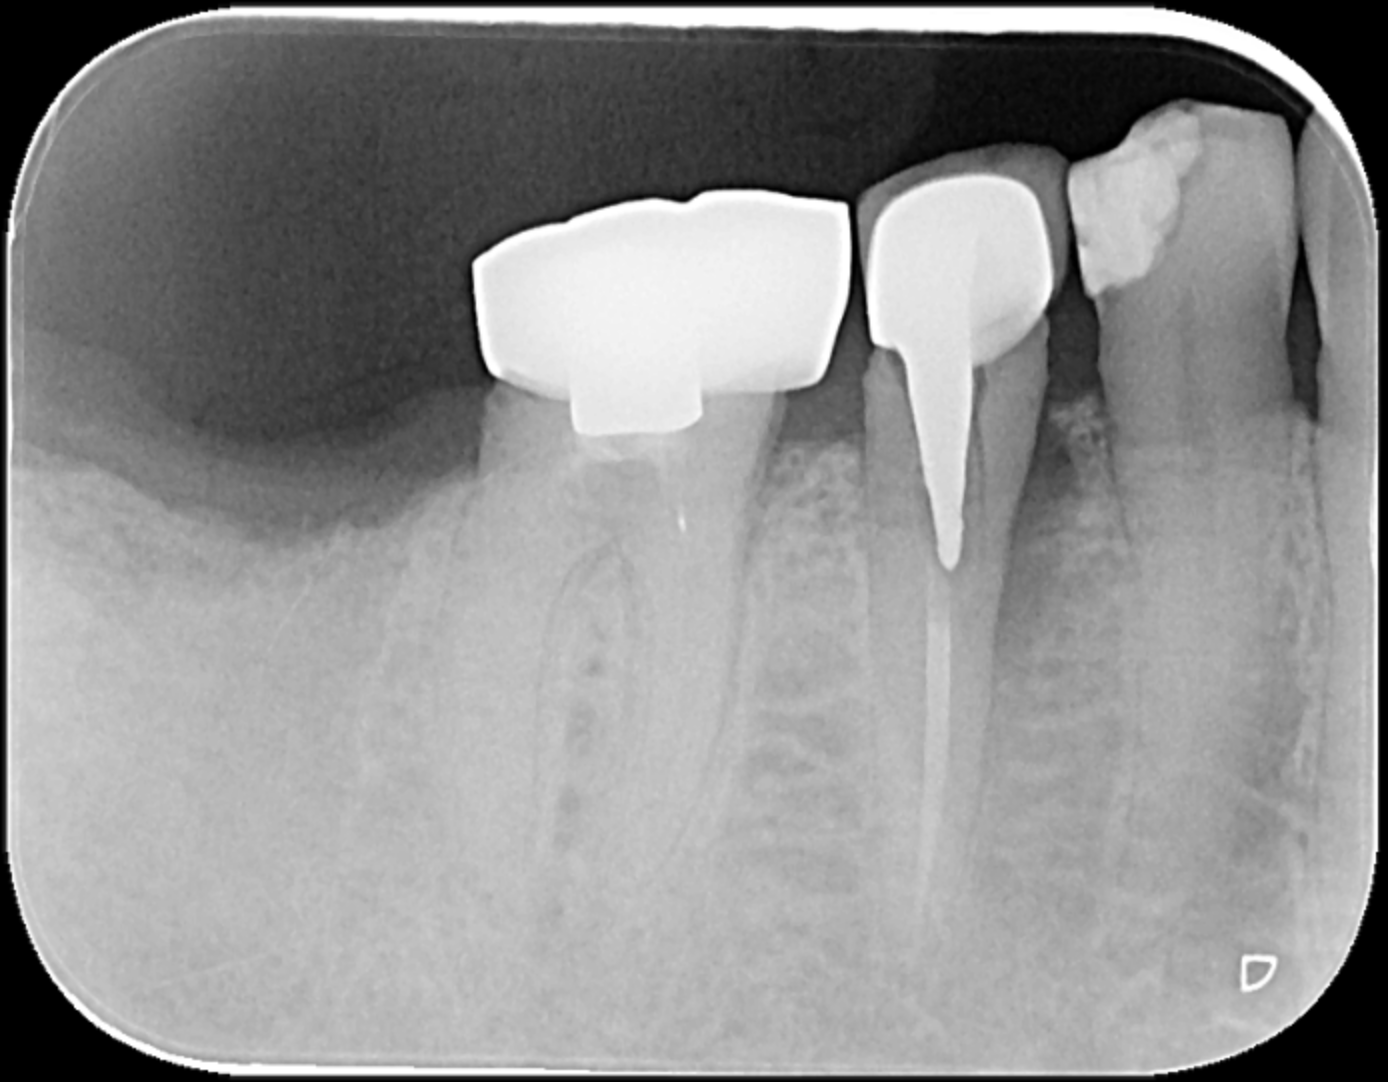

「王醫師,我中午吃便當時不小心咬到骨頭,突然間牙齒好痛,張口一看,牙齒被我咬斷了,我該怎麼辦?」A先生手裡拿著斷裂的那片牙齒,至北市聯醫仁愛院區牙科門診尋求協助,希望牙醫師能夠幫他把斷裂的碎片黏回,經過口內及影像檢查後,診斷為牙根垂直縱裂。牙醫師當下告知病人這顆牙齒無法保留,病人了解並且同意下決定當日拔除牙齒,解決了病人疼痛的問題。

王君翎解釋,假如牙齒斷裂位置已經從牙冠延伸到牙根,屬於比較嚴重的狀況,這類的牙齒大部分都必須拔除,以避免後續的發炎、腫脹。缺牙區域可考慮以固定式牙橋或人工植牙重建,恢復美觀及咀嚼功能。少部份斜裂到牙根的牙齒,斷裂位置靠近牙根頂端接近牙冠的部位,牙根有足夠長度,且牙周狀況良好,此時可考慮作牙冠增長術或局部牙齦切除,以利於日後假牙牙冠的製作。

,當日拔除.jpg)